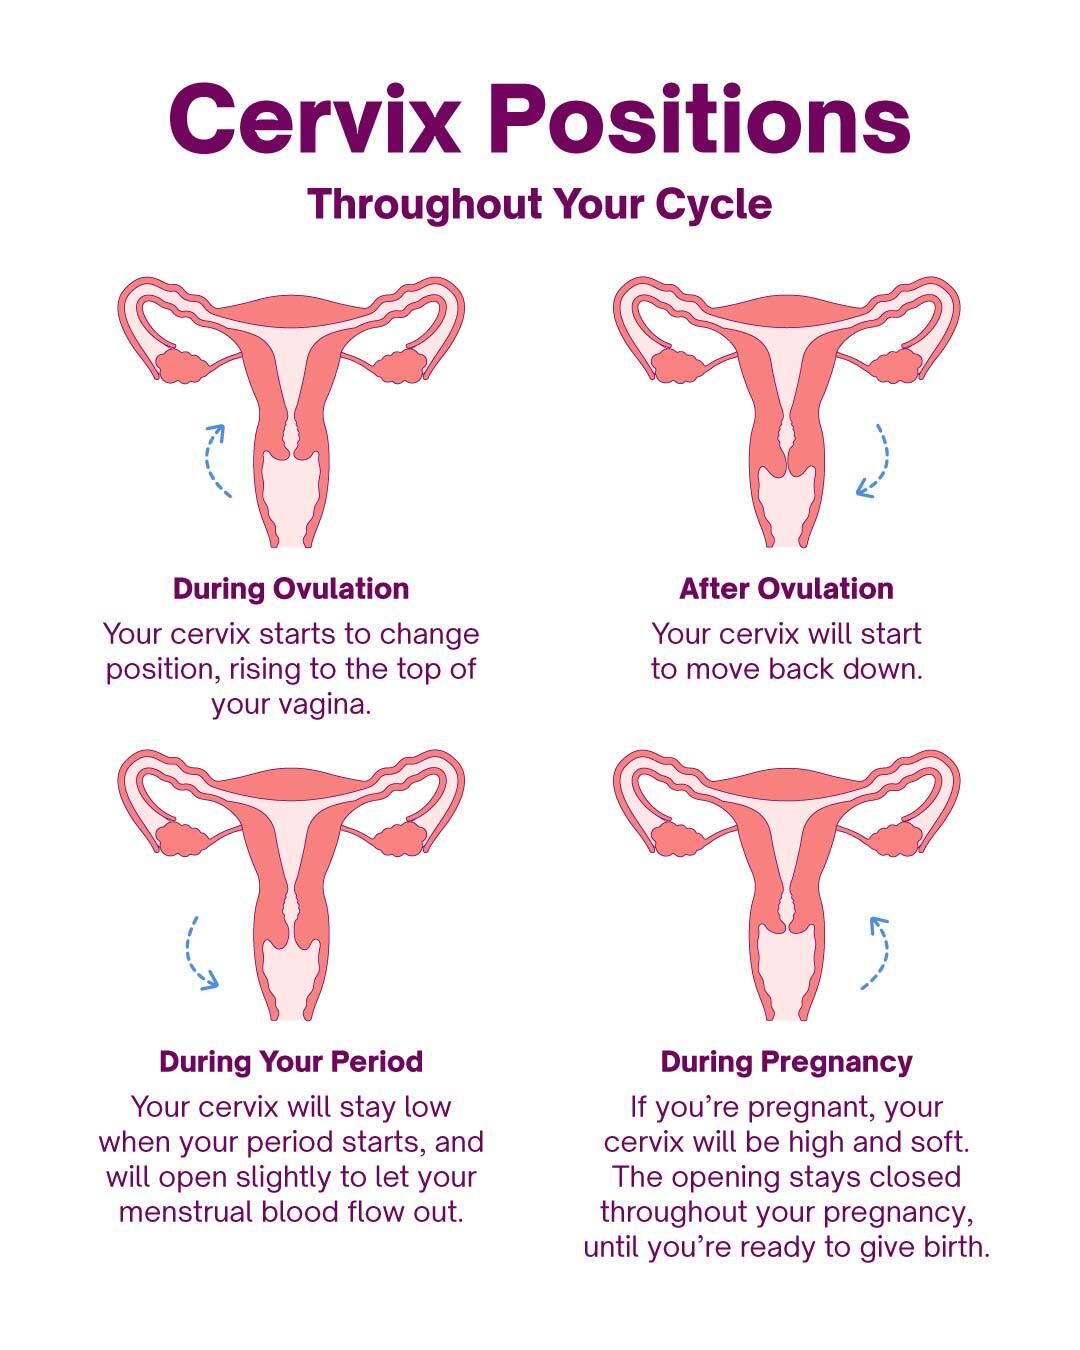

How Can You Tell If Cervix Is Open Or Closed Discount Cfasouthern

Cervix Before And During Pregnancy